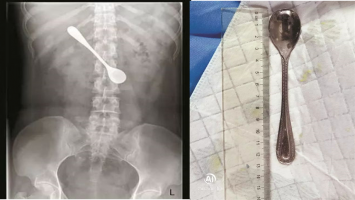

Baca Juga: Coba Hilangkan Tulang Ikan di Tenggorokan, Wanita Ini Malah Telan Sendok

"X-ray dan CT scan dilakukan tetapi penyebab rasa sakit tidak dapat dipastikan," jelas dr. Praveen Aggarwal, dokter yang menangani Avid.

Ketika dokter melakukan CT scan di perut, terdapat benda asing yang bersarang di perut pria tersebut. Saat itulah Avid akhirnya mengaku kalau ia tak sengaja menelan sikat gigi.

CT scan lain dilakukan untuk memeriksa apakah sikat tersebut menyebabkan kerusakan pada organ dalam Avid atau menyebabkan perforasi.

Operasi pun harus segera dilakukan. Pada 10 Desember, sikat gigi tersebut diangkat dari perut pria India itu melalui operasi endoskopi.

Untungnya, sikat gigi ini tidak menyebabkan luka atau kerusakan pada organ dalam Avid.